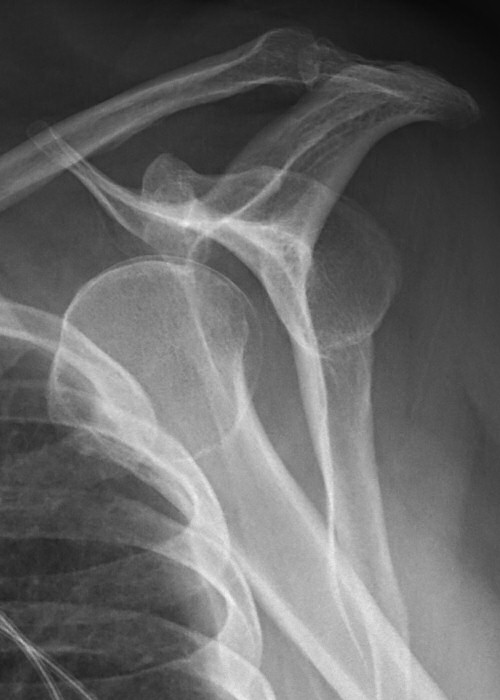

Främre luxation

Efter reponering